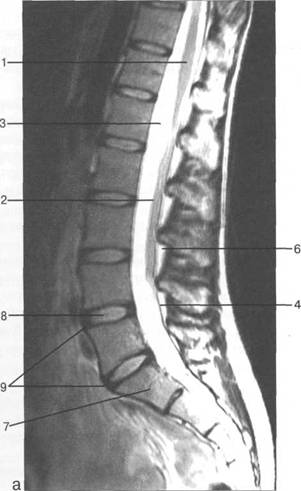

Lv-S,.

Lv; S,; S;; Lv.

8

9

L^

LIV; L^; Lv; LIV;

Lv Sp S,

MPT.